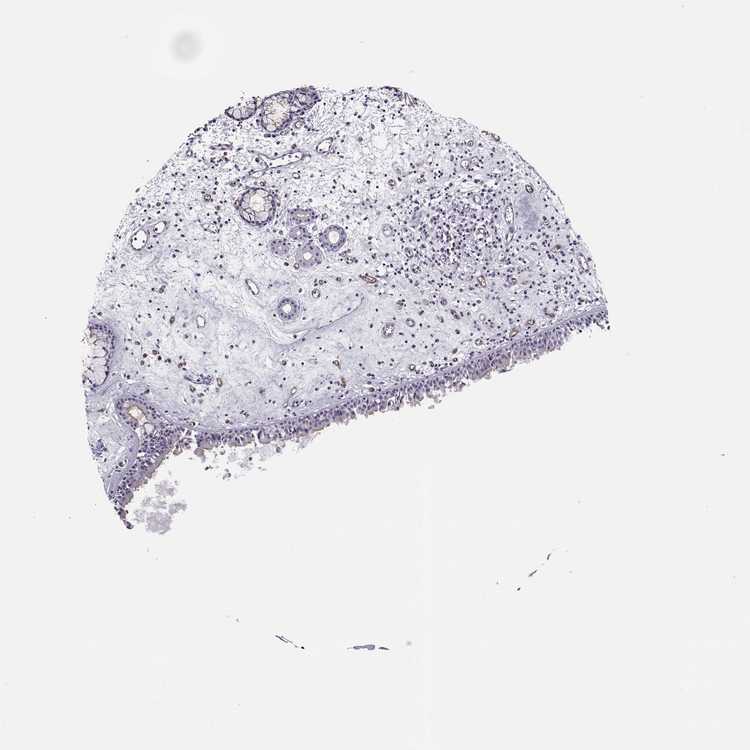

TISSUE PRIMARY DATA NASOPHARYNX Show tissue menu

NASOPHARYNX - Antibody stainingi

Antibody staining in the annotated cell types in the current human tissue is reported as not detected, low, medium, or high, based on conventional immunohistochemistry profiling in selected tissues. This score is based on the combination of the staining intensity and fraction of stained cells.

Each image is clickable and will lead to virtual microscopy that enables deeper exploration of all samples and also displays staining intensity scores, fraction scores and subcellular localization as well as patient and tissue information for each sample.

Antibody HPA001672Antibody HPA066520

Respiratory epithelial cells HighLow